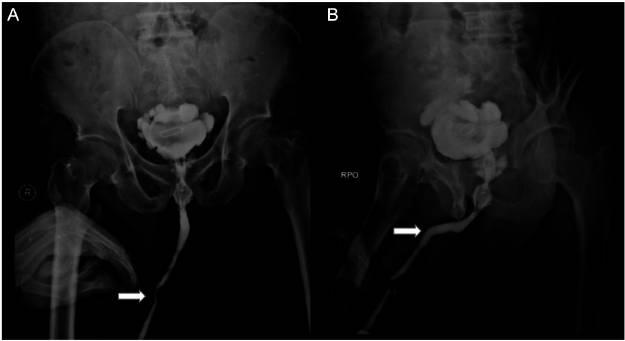

体格检查显示无耻骨上压痛、隆起或肿块。血液检查显示轻度贫血,血尿素氮升高为171 mg/dL(19.3-49.2 mg/dL),血肌酐升高为12.4 mg/dL,提示严重肾功能衰竭。尿液分析见白细胞和红细胞,提示尿路炎症。腹部X光片显示盆腔有一不透光异物及一个类似金属丝的线性不透光阴影(图1)。尿道造影显示充盈缺损和尿道扩张(图2)。CT扫描证实双侧肾积水和输尿管积水,以及大小为4.4×3cm的膀胱结石。大小为1.9×1.2cm的尿道结石也显著可见,并伴有类似金属丝的线性异物(图3)。CT扫描证实为梗阻性肾病。

图2 尿道造影显示膜段有充盈缺损和尿道扩张